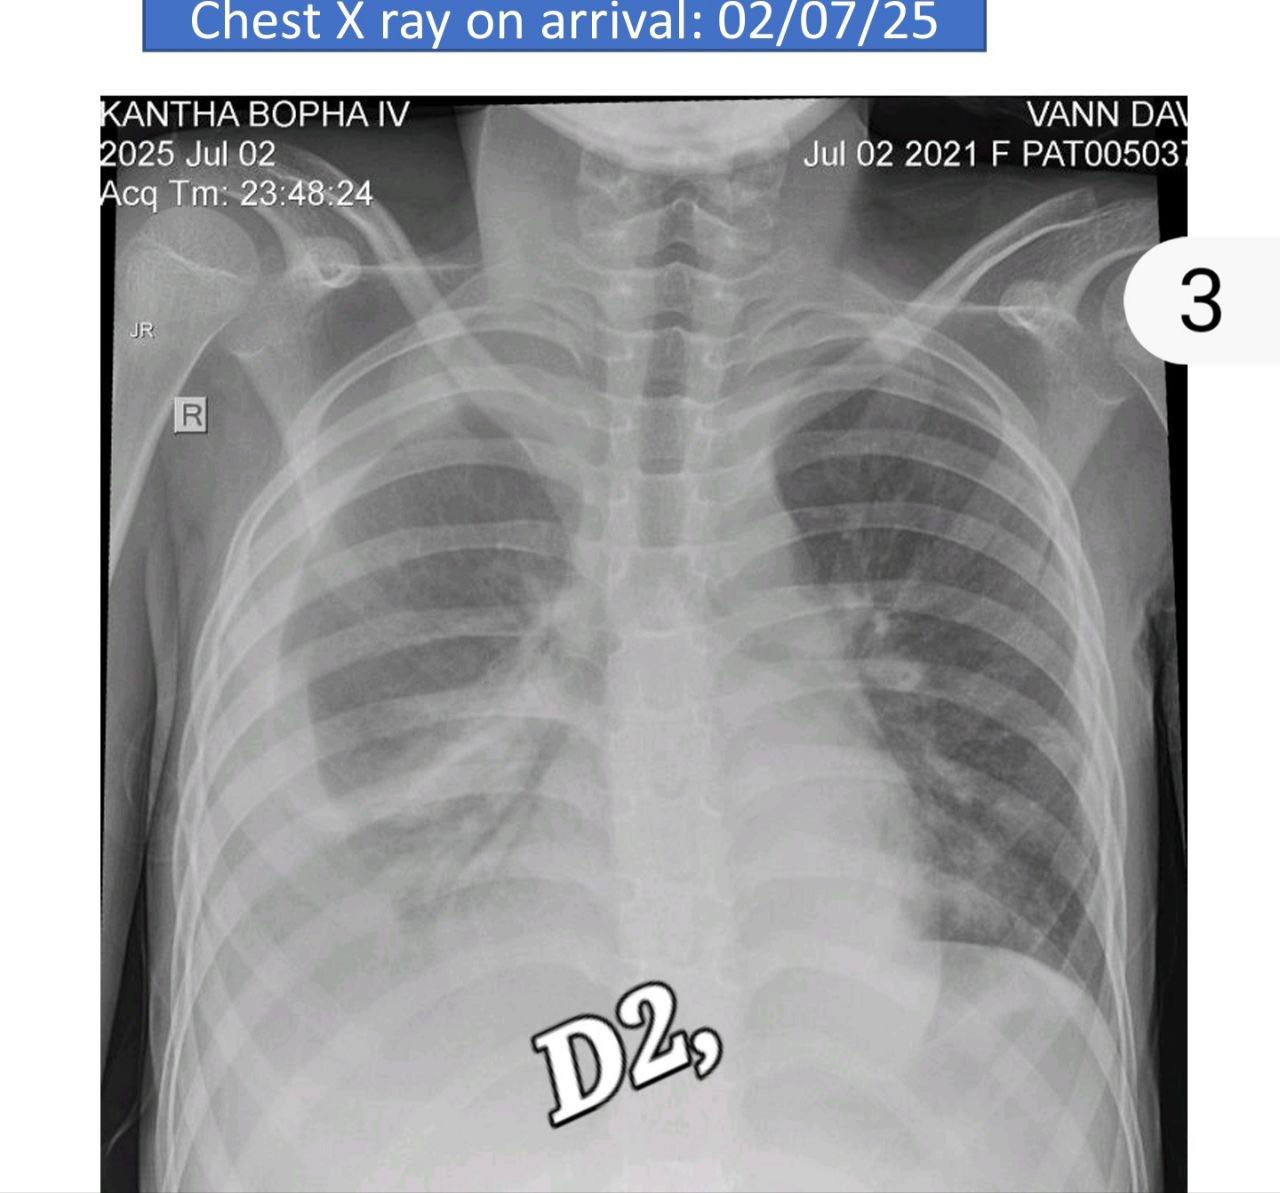

កុមារីម្នាក់នេះ អាយុ ៩ឆ្នាំ ត្រូវបានព្យាបាលជំងឺគ្រុនឈាមនៅឯគ្លីនិកឯកជនមួយអស់សេរ៉ូម៣លីត្រ ក្នុងខេត្តត្បូងឃ្មុំ បានមកដល់មន្ទីរពេទ្យគន្ធបុប្ផា ពេលជំងឺវិវត្តន៍ធ្ងន់ធ្ងរនៅដង្ហើមចុងក្រោយ។

កុមារីមានជំងឺគ្រុនឈាមកម្រិតធ្ងន់ធ្ងរបំផុត (EDS): អស់ជីពចរ (shock syndrome) បែកគ្រាប់ឈាម និងហូរឈាមក្នុងក្រពះពោះវៀន និងខ្សោយថ្លើម-តម្រងនោម (DSS induced HUS)។ កុមារី ត្រូវបានសង្រ្គោះជីវិត ដោយប្រើឈាមច្រើនប្លោក-និងជំនួយម៉ាស៊ីន សប់ដង្ហើម ៦ថ្ងៃ និងសម្រាកពេទ្យរយ:ពេល២០ថ្ងៃ។ ថ្ងៃនេះកូនស្រី មានជីវិតរស់ឡើងវិញ និងបានត្រឡប់ទៅផ្ទះវិញ ដោយស្នាមញញឹម។